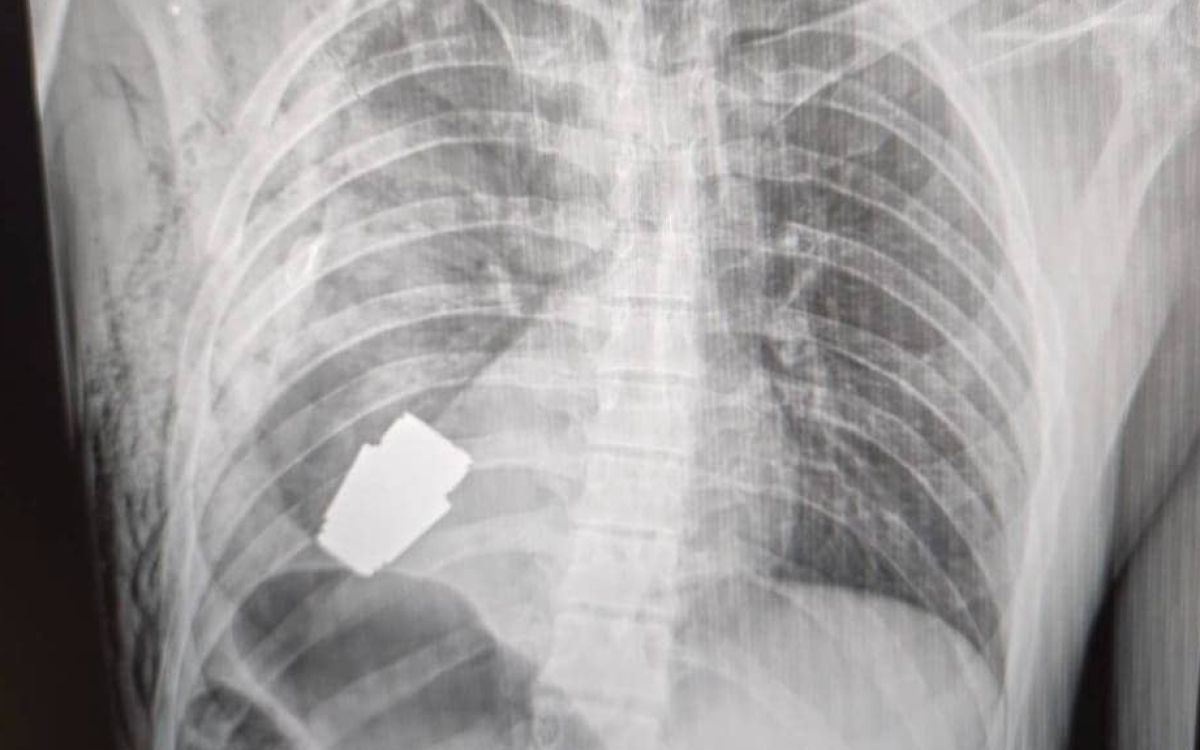

Zelo delikatno operacijo je pred dnevi izvedel eden najboljših ukrajinskih vojaških kirurgov Andrii Verba. »To je operacija, ki bo šla v medicinske učbenike,« je dejal Anton Geraščenko, svetovalec notranjega ministra. Verba je namreč operiral ranjenega ukrajinskega vojaka, ki ga je v prsi zadela ruska granata tipa VOG. Zarila se mu je globoko v prsni koš in se ustavila tik pod srcem, a kot po čudežu ni eksplodirala.

V operacijski dvorani sta bila poleg zdravniškega osebja, ki ni smelo uporabljati električnih naprav, saj bi lahko te sprožile detonacijo granate, tudi dva strokovnjaka za deaktiviranje, ki sta poskrbela za varnost zdravnikov in nevtralizirala ubojno sredstvo. Spretnost kirurgov in ekspertiza vojaških strokovnjakov so poskrbeli, da so tako pacient kot osebje in bolnišnica ostali celi.

Ukrajinska namestnica ministra za obrambo Hanna Maliar je potrdila uspešnost operacije: »Vojaški zdravniki so uspešno opravili operacijo, s katero so odstranili neksplodirano granato iz telesa vojaka. Ta bi se lahko prožila v kateremkoli trenutku.« 28-letni vojak je preživel, njegovo stanje je stabilno in je zdaj na rehabilitaciji.